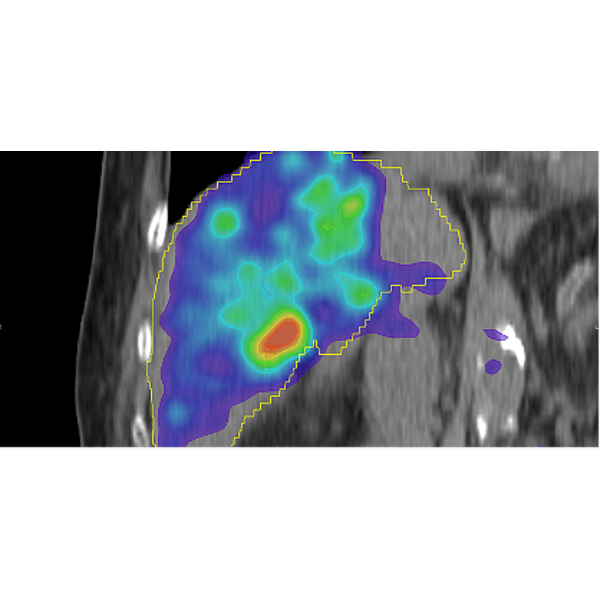

Post-Therapy Dosimetry

MIM SurePlan LiverY90 provides tools for dose calculation using Y90-PET and Bremsstrahlung SPECT. This allows you to calculate isodose curves/DVH on PET/SPECT using Local Deposition Method or the Voxel S Value approach based on the schema in MIRD Pamphlet No. 17. Therapy response evaluation is possible with automated tools for serial exam comparison.